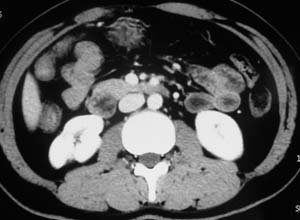

以下是引用子期在2010-3-19 20:47:00的发言:[br]血管畸形的ct增强应该有明显强化,本例并不相符合。本例双肾局部的略低密度影,累及肾盂,局部皮质明显变薄、内陷,增强扫描有轻度的强化,应考虑为炎性病变,患者为年轻男性,累及双肾的感染以结核较常见,可以没有明显的临床症状,尿中有时候也并不能查出什么;肾脓肿常有明显感染中毒症状,本例不符,另外一般的肾盂肾炎或肾小球肾炎通过小便就可确诊,其它还不能排除的是黄色肉芽肿性肾盂肾炎,然而单凭ct一般也很难鉴别。